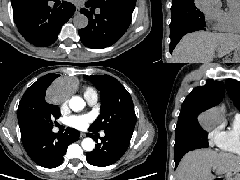

4、增强后不均匀强化,存在低强化区呈弱强化或无强化,因此可见“血管造影征。”血管毛糙与肺炎有统计学差异。

三、本例是一个误诊多年的病例,给我们很多启示:

1.多学科探讨的重要性:肾内科忽视肺部病变,后续需要呼吸、影像、病理共同探讨。

2.粘液腺癌易伪装成肺炎的形态,尤其是当患者本身具有免疫色彩的时候,易误诊为间质性肺炎,或肺部感染。若治疗无效,取得病理很重要。